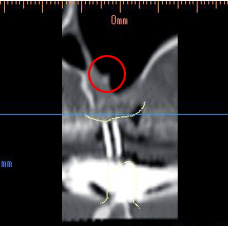

治療前のCTは医科用です。内側には骨があるのですが、全体的に上顎洞まで骨が3mmしかなくサイナスリフトによる骨造成が必要です。

ポイントは埋入部分の内側に小さな隔壁(骨の突起)があることです。

内側の骨をねらって傾斜埋入もあると思いますが、リスクが大きいです。